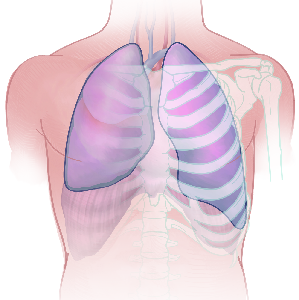

Detailreiche Fotografien aus der medizinischen Praxis ergänzen die Texte; moderne, genaue,

wissenschaftliche Zeichnungen geben Einblick in die Anatomie und die Funktion der Lunge und

anderer Organe.